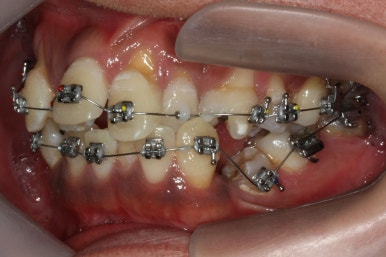

치료 8개월째의 모습입니다.

이제 얼핏 보면 매우 가지런해졌어요. 이 뽑은 자리도 많이 남지 않았고 왼쪽 위 송곳니가 없지만 그리 표시도 많이 나지 않네요.

대신 위쪽 아래 작은 어금니가 애를 먹이고 있어요. 낚시줄처럼 부여매고 끌어올리는게 보이실거에요.

뼈에 단단히 붙어 안움직이는 경우를 "유착치아"라고 표현하는데, 유착치아라면 해당 치아를 움직이는 것을 포기했어야 했어요.

그래도 조금씩이라도 움직이고 있어서 계속 시도했습니다.